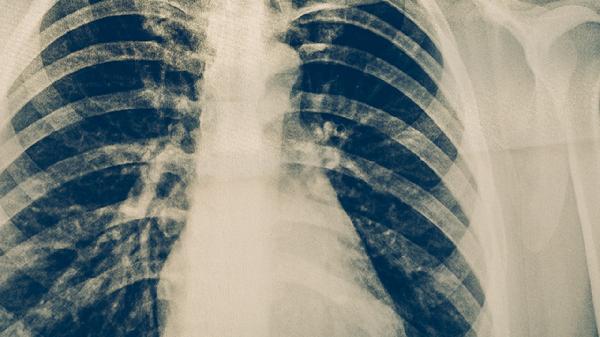

肺癌胸腔積液可通過胸腔穿刺引流、胸腔閉式引流、藥物治療、放射治療、手術(shù)治療等方式緩解。肺癌胸腔積液通常由腫瘤侵犯胸膜、淋巴回流受阻、低蛋白血癥、感染、心力衰竭等原因引起。

對(duì)放療敏感的腫瘤類型如小細(xì)胞肺癌,可對(duì)胸膜病灶進(jìn)行局部放療,減少腫瘤對(duì)胸膜的刺激。放療可能引起放射性胸膜炎,導(dǎo)致暫時(shí)性積液增多,需配合利尿劑如呋塞米片緩解癥狀。治療期間應(yīng)定期復(fù)查胸部CT評(píng)估療效。